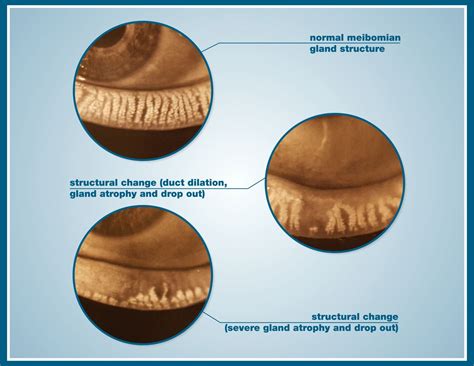

Meibomian Eye Gland Dysfunction occurs when the meibomian glands become blocked or inflamed, leading to a reduction in the production of the oily layer of the tear film. This oily layer is essential for preventing the evaporation of tears and maintaining the stability of the tear film. When this layer is compromised, it can result in dry eyes and other related symptoms.

Diagnosing Meibomian Eye Gland Dysfunction typically involves a comprehensive eye examination. The eye care professional may perform the following tests:

• Slit-Lamp Examination: This involves using a specialized microscope to examine the eyelids and meibomian glands for signs of blockage or inflammation.

• Meibomian Gland Expression: This involves gently squeezing the meibomian glands to assess the quality and quantity of the oil produced.